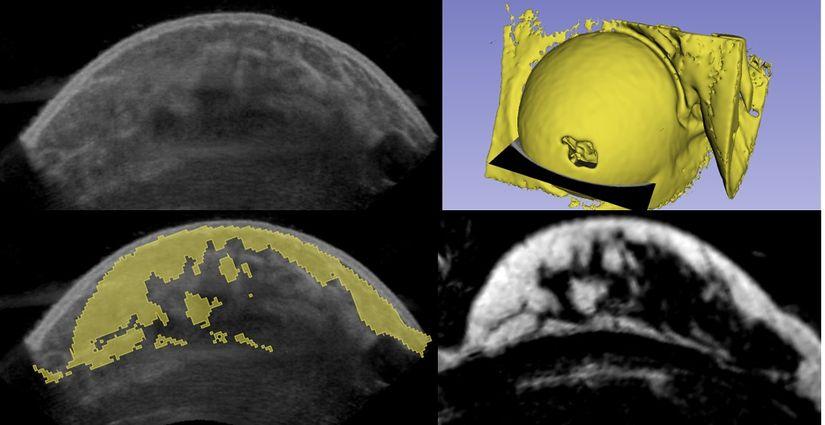

We developed different scanning approaches. Results show volumetric images of a custom-developed phantom, scanned with an ultrasound transducer mounted on a robotic arm (top) and with a transducer integrated in the wall of an automatically rotating cone-shaped container (bottom). More results of the cone-based volumetric ultrasound breast imaging scanner have been published in (Nikolaev, 2021)

Volumetric imaging of the breast volumetric phantom with the robotic arm (top) and automated cone-shaped container (bottom). From left to right: the imaging setup(a, d), rendered volumetric data (b, e), and coronal cross-sectional image (c, f).

Subsequently, we co-registered in-vivo MRI and 3D US data in a volunteer with a benign lesion (fibroadenoma) and a cyst. The same cross-sections were taken for clear observation of the fibroadenoma and the cyst. Dark areas in US images represent fat, while bright areas represent glandular tissue. Both fibroadenoma and cyst are visible as dark spots and pointed out with arrows. In the MRI images (T2 sequence Dixon protocol, fat), glandular tissue is represented as a shaded area while bright represents fat. Both lesions are visible and characterized by dark spots. The skin layer is occult in the utilized MRI image.

MRI-3D US image fusion of a breast. a) Rendered MRI data with indicated cross-sectional transversal plain. b) Cross-sectional US image. b) Cross-sectional MRI image. c) MRI data overlayed 3D US data.